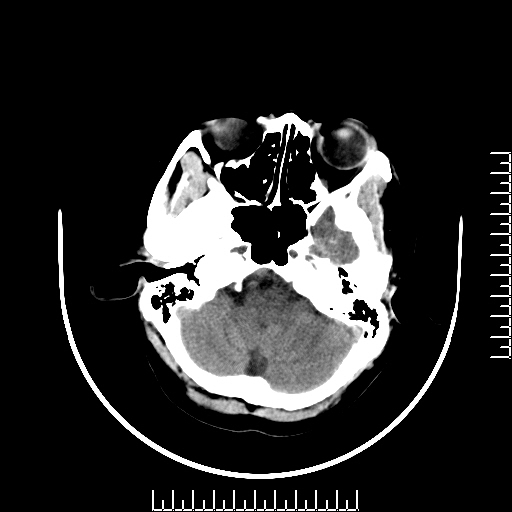

CT50772:颅内病变,病理结果已公布

本帖最后由 cefcmj 于 2015-7-10 08:31 编辑   (结果连接:http://www.radida.com/bbs/forum. ... d=126554&extra=) 患者性别:女 患者年龄:37岁 醉酒后出现头晕沉不适10余天,伴乏力,嗜睡。为 ...

从仅有的CT平扫图像看,只能诊断鞍区实性肿瘤,鞍区肿瘤常为垂体瘤、颅咽管瘤及脑膜瘤多见,增强扫描有助于帮助鉴别。

颅咽管瘤,蛋壳样钙化吧

[病理诊断] CT50772:颅咽管瘤。